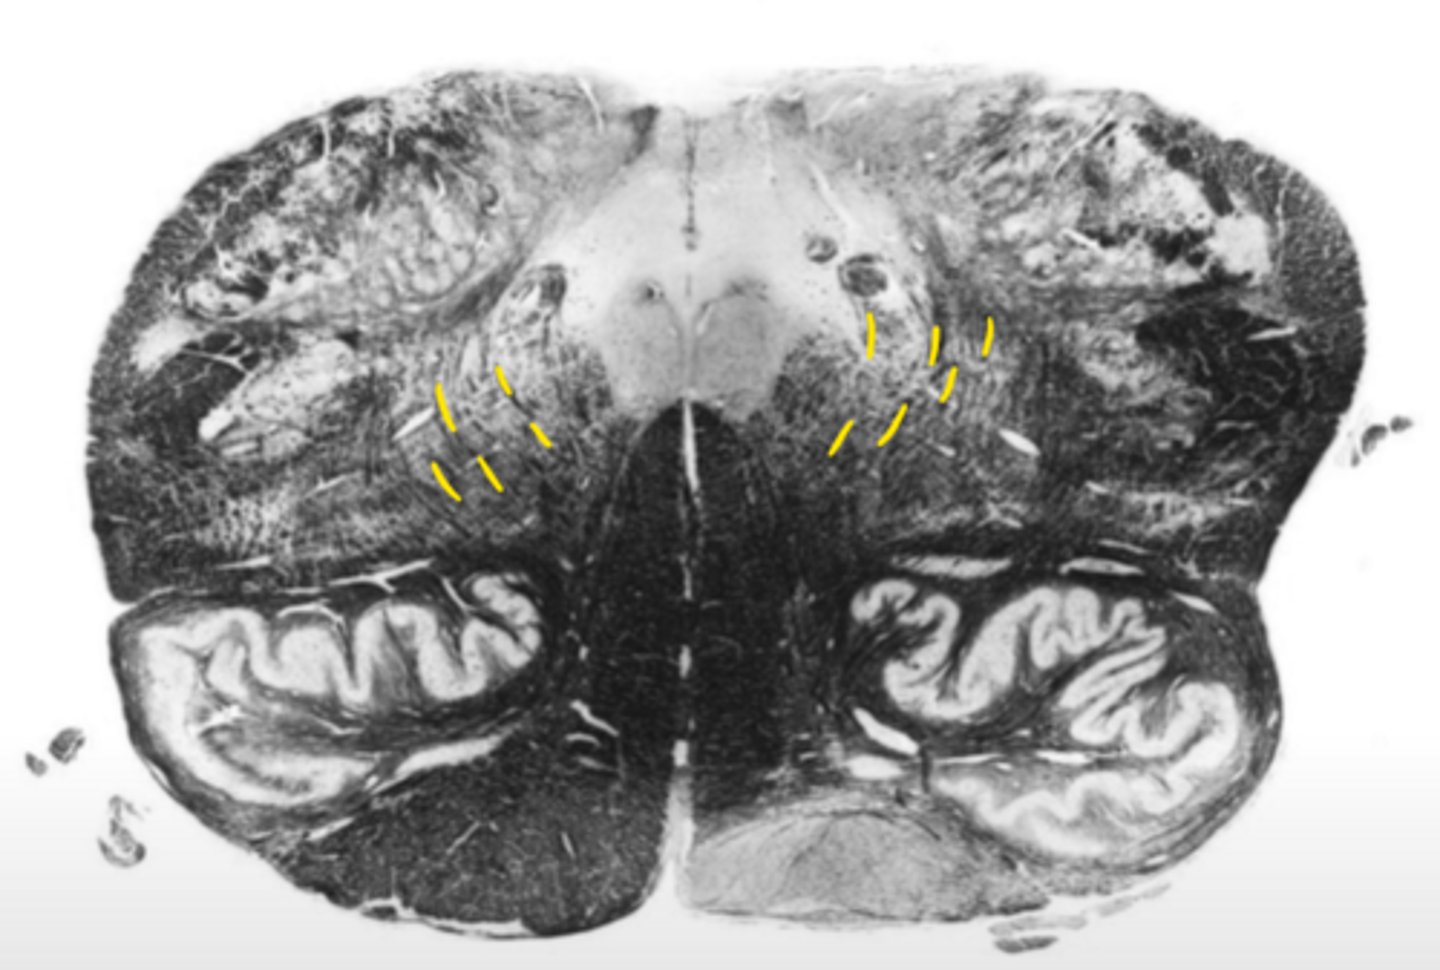

posterior median sulcus

ID the structure

hypoglossal nucleus

ID the nucleus

central gray

gracile nucleus

posterior intermediate sulcus

cuneate nucleus

ID the light area

cuneate fasciculus

ID the dark area

internal arcuate fibers

medial lemniscus

principle olivary nucleus

corticospinal fibers

anterior median sulcus

gracile fasciculus

posterior lateral sulcus

spinal accessory nucleus

descending motor pathways

motor decussation

central canal

closed medulla

ID the brainstem level